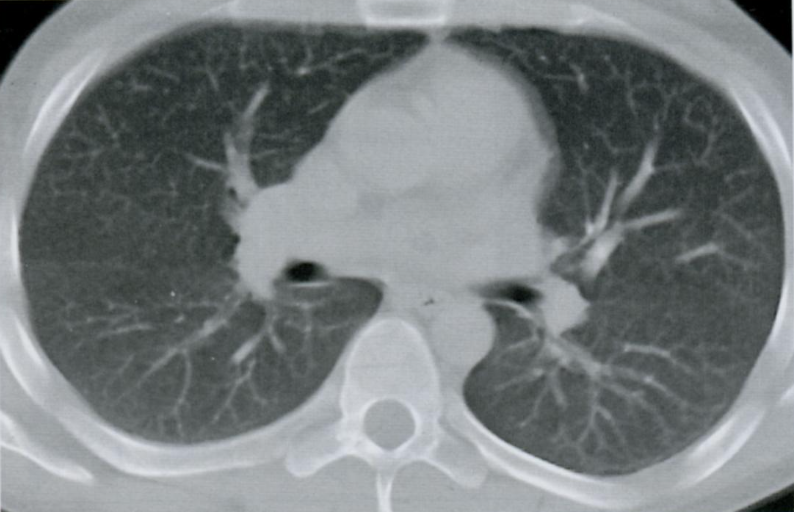

КТ грудной клетки №3

Назовите все анатомические структуры, которые Вы знаете, на данном КТ срезе (10).

Найдите грудные позвонки и грудину. Затем верхнюю полую вену, восходящую и нисходящую аорту, легочный ствол, левое предсердие и легочные сосуды, непарную вену и пищевод.

A

26 - грудные позвонки

24 - грудина

1 - верхняя полая вена

7 - восходящая аорта

9 - легочный ствол

3 - левое предсердие

10 - сосуды легких

8 - нисходящая аорта

15 - непарная вена

16 - пищевод

Синим цветом отмечены номера сегментов.